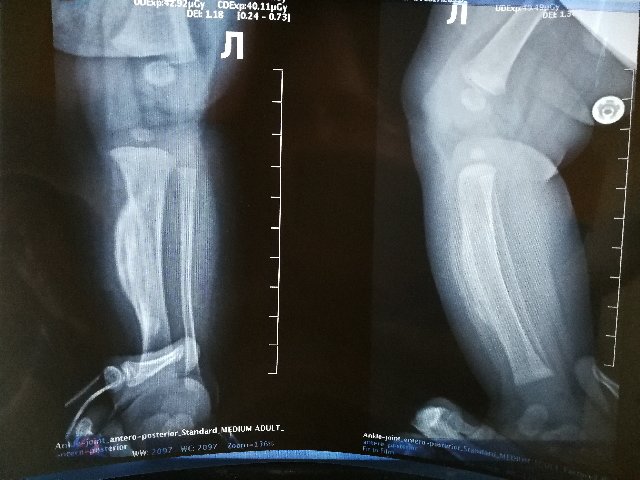

Гиперостоз на месте, искривление голени присутствует, но уменьшается. Ребенку не мешает. В тот раз не приложились снимки, прикладываю для истории снова.

Слева легкий вальгус. Сохраняется зажимание указательных пальцев, особенно слева, в играх на мелкую моторику.  Учу контролировать. Все равно предпочитает правую сторону.